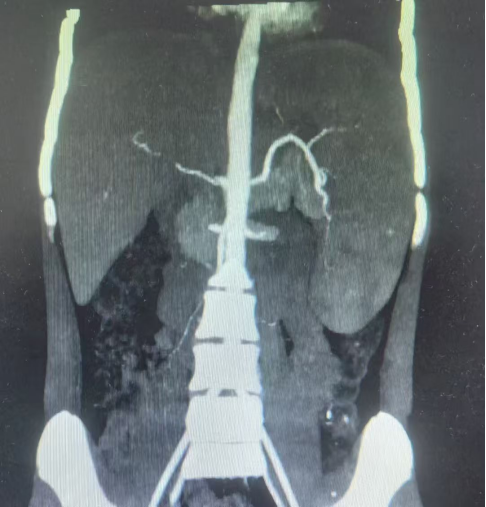

此次接受手术的患儿均为地中海贫血伴脾肿大,经小儿外科团队详细评估,患儿均符合脾切除手术指征,但考虑到儿童腹腔空间狭小、组织娇嫩,且家长对术后美观及康复速度有较高期待,团队决定采用“单孔腹腔镜技术”——仅在患儿脐部切开一个约2cm的小切口,通过专用器械完成脾脏游离、血管结扎及完整切除,最后将脾脏组织经脐部切口取出。

“单孔腹腔镜手术的关键在于‘精准’与‘协调’。”我院小儿外科主任窦俊锋介绍,脾脏血供丰富,周围毗邻胃、胰腺、结肠等重要器官,儿童腹腔操作空间仅为成人的1/3左右,术中需通过单一通道完成分离、止血、结扎等多步骤操作,对团队的解剖熟悉度、器械配合能力及应急处理水平要求极高。